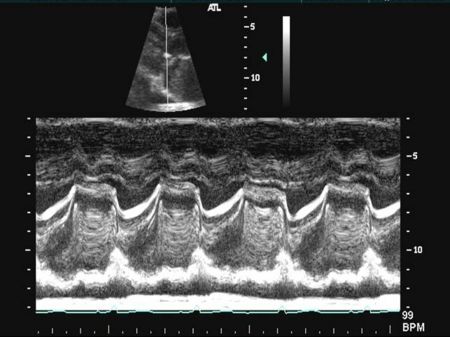

Aortic Valve M-mode Analysis

- During systole do the aortic valve leaflets oppose the aorta?

- Are the leaflets thick and calcified (bright)?

- Possible to have normal appearance on m-mode if non-calcific

- Are leaflets open throughout systole - HOCM, low-output state